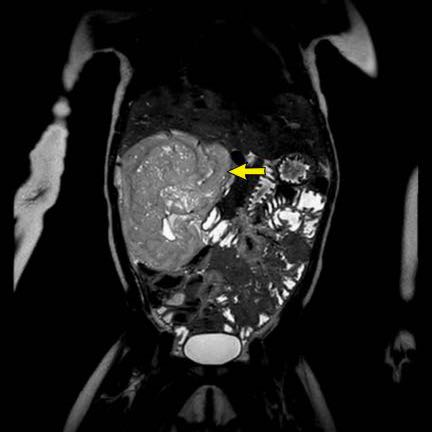

Hình ảnh chuỗi xung T2W mặt phẳng coronal cho thấy một khối u không đồng nhất ở thận trái với các thành phần nang nhỏ.

Khối u ngấm thuốc kém hơn so với phần nhu mô thận bình thường còn lại ở ngoại vi.

Các thành phần đặc của khối u cho thấy hạn chế khuếch tán rõ rệt (mũi tên).

Đây là u Wilms ở bé trai năm tuổi. Hóa trị tiền phẫu được thực hiện theo phác đồ Umbrella của SIOP-RTSG, sau đó tiến hành cắt thận.